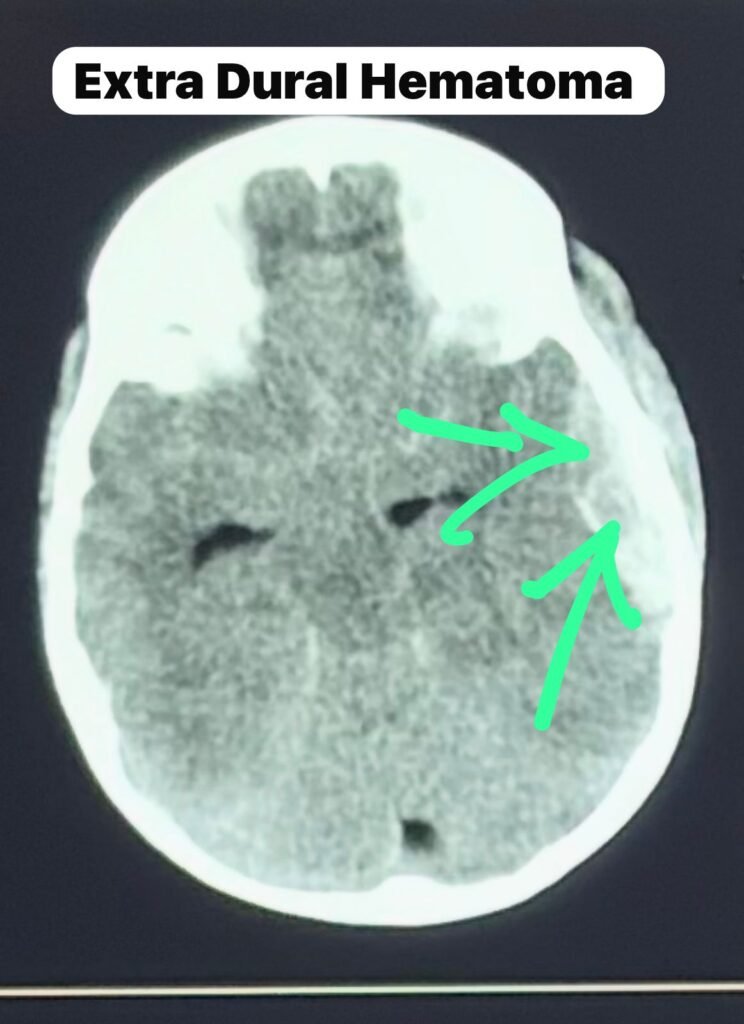

CT Scan Findings: A Surgical Emergency

The CT scan showed:

• Large left temporoparietal extradural hematoma

• Temporal bone fracture

• Significant midline shift

• Severe mass effect

The CT scan confirmed acute arterial EDH with impending brain herniation. Immediate neurosurgical intervention in Bengaluru was required.